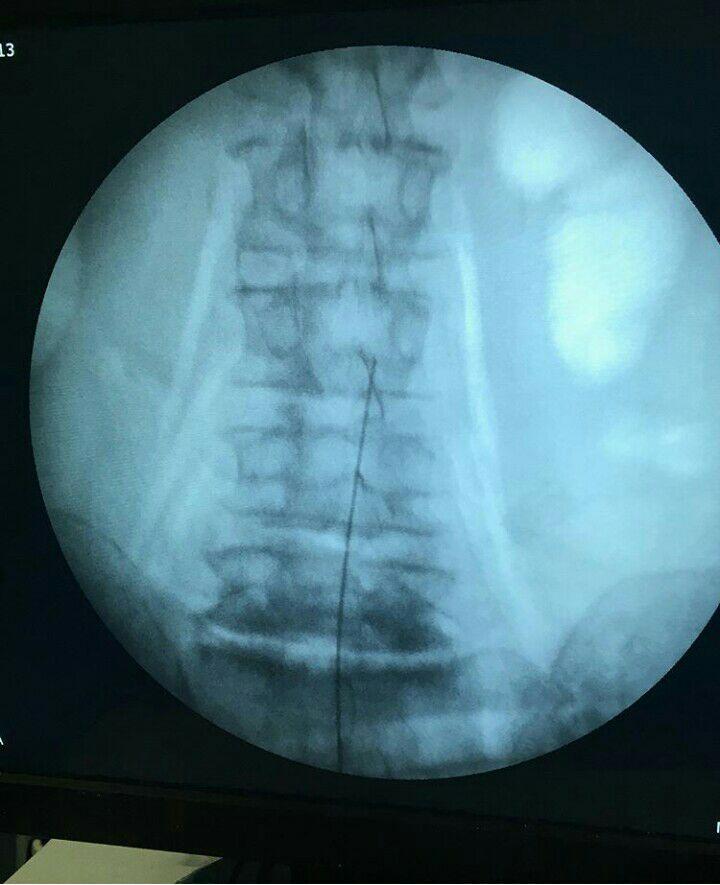

-لیزر(جراحی بسته) دیسک کمری

-درمان تنگی کانال نخاعی غیرقابل جراحی

استفاده از روشهایی مانند تزریقات تخصصی (مانند اپیدورال، بلوک عصبی)، طب سوزنی، فیزیوتراپی، تحریک الکتریکی عصب و روشهای کم تهاجمی جراحی.